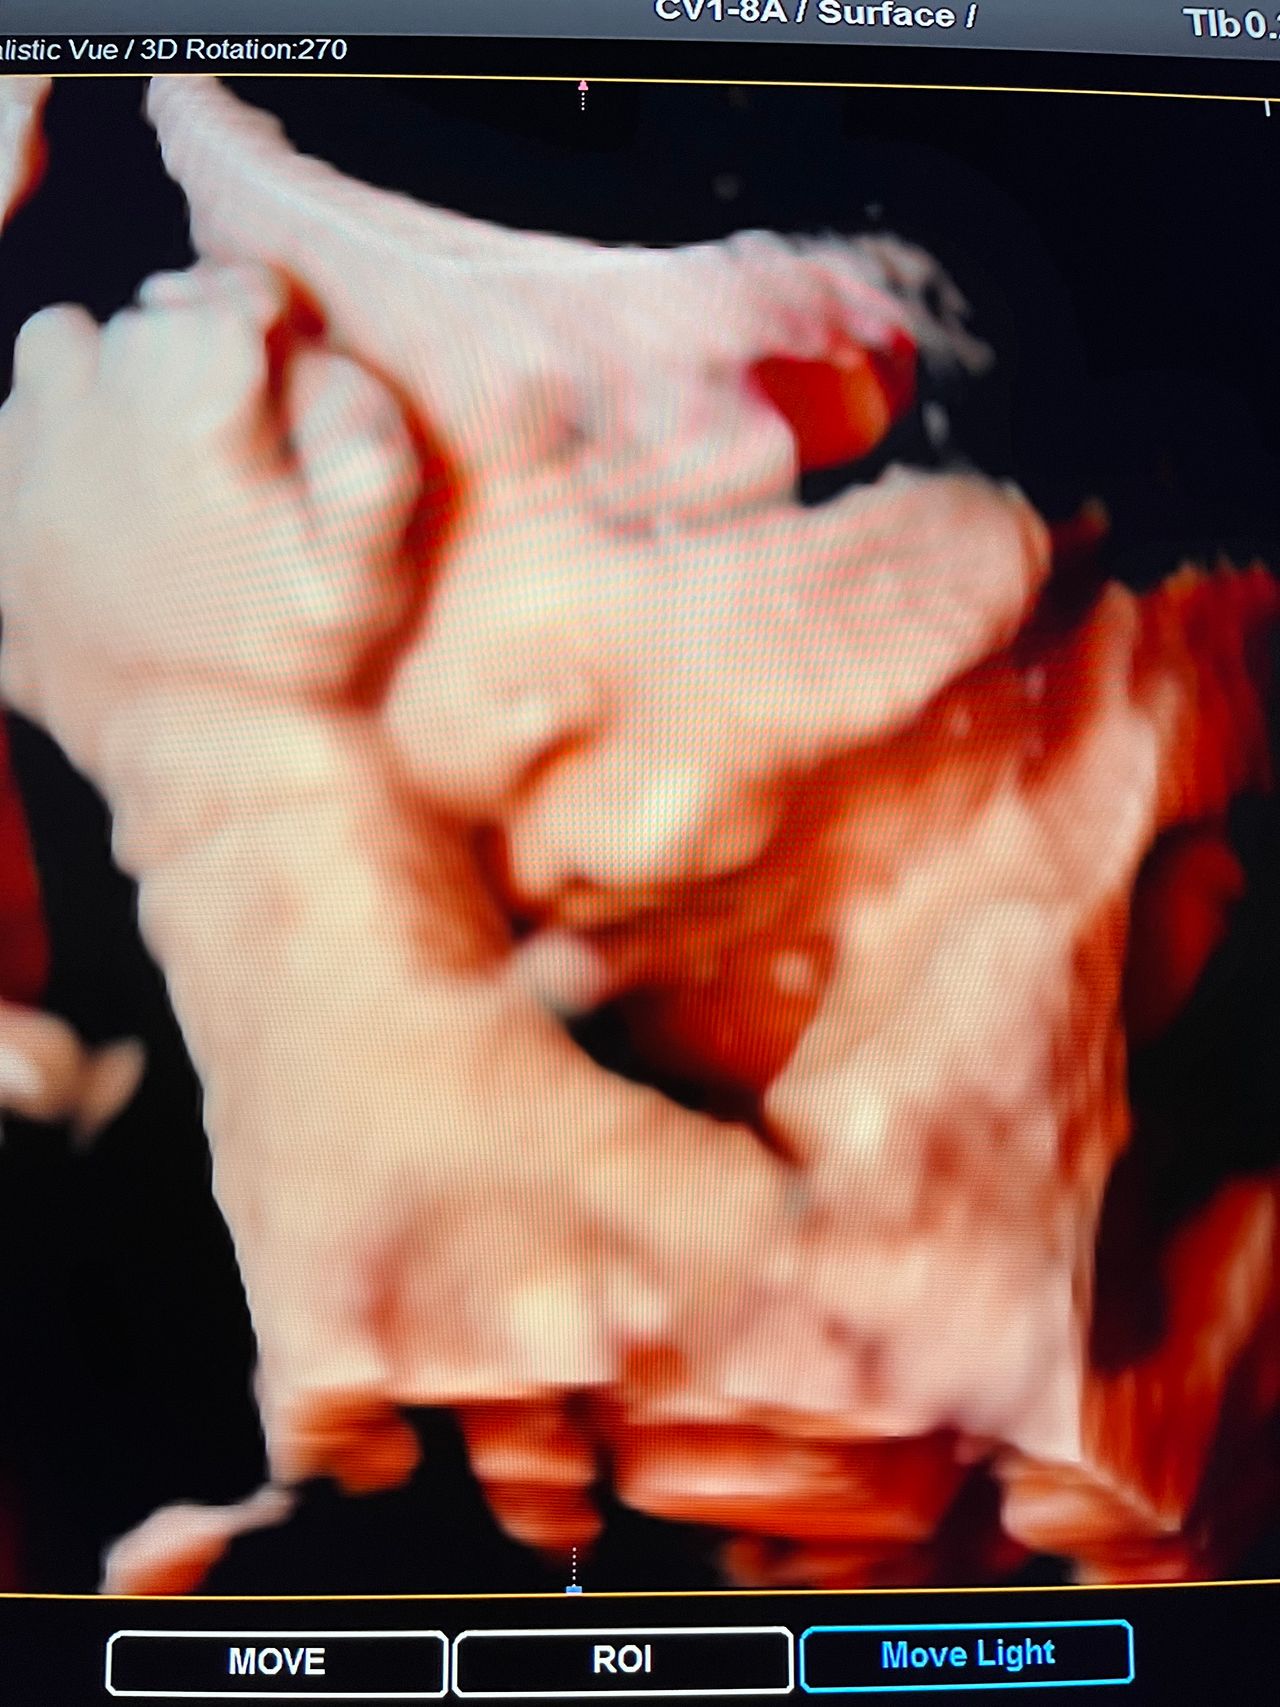

Attualmente lavoro come Dirigente medico nella SC di Ostetricia e Ginecologia dell'Ospedale Michele e Pietro Ferrero di Verduno, mi occupo prevalentemente di screening prenatale, ecografia ostetrica del I trimestre( misurazione translucenza nucale,NT), ecografia morfologica del II trimestre, ambulatorio pregresso taglio cesareo, ecografia ostetrica 3D. Seguo le gravidanze fisiologiche e quelle ad alto rischio , presto servizio in sala parto. Eseguo visite ginecologiche di I-II livello in regime ambulatoriale, counseling contraccettivo ed eventuale prescrizione pillola, inserimento spirale (IUD), dispositivo sottocutaneo (Nexplanon).

Foto e video